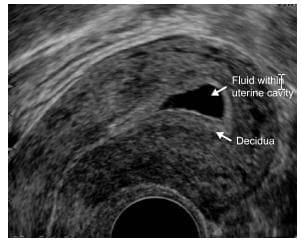

Uterine cavity expanded with fluid mimicking an intrauterine